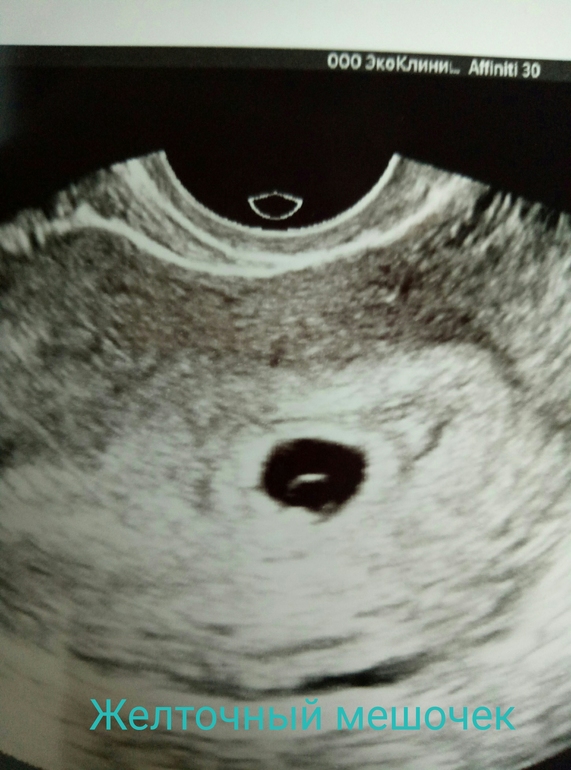

Я БЕРЕМЕННА !Еле дождались дня узи.😊 Еще и страшно неимоверно. В полости матки одно плодное яйцо 10мм с четкими ровными контурами,жм 3.2мм,эмбрион визуализируется ,сб+ ,жт 12мм .Акушерский срок 5нед

5дней. Вот она моя рыба) ни одного теста в этот раз не сделала)